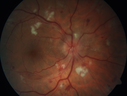

Grade 4 hypertensive retinopathy456 views55 year old man Hhe did have headaches a few weeks ago and also some nausea and vomiting. He noticed for a few weeks the vision in the left eye was blurred and that the vision in the left eye is dark.

VA OD: Dcc20/20

VA OS: Dcc20/100-1

He was admitted directly to ICU for blood pressure control (290 / 170 mmHg)

3 weeks later his VA increased to 20/20 OD, 20/32 OSJan 29, 2019